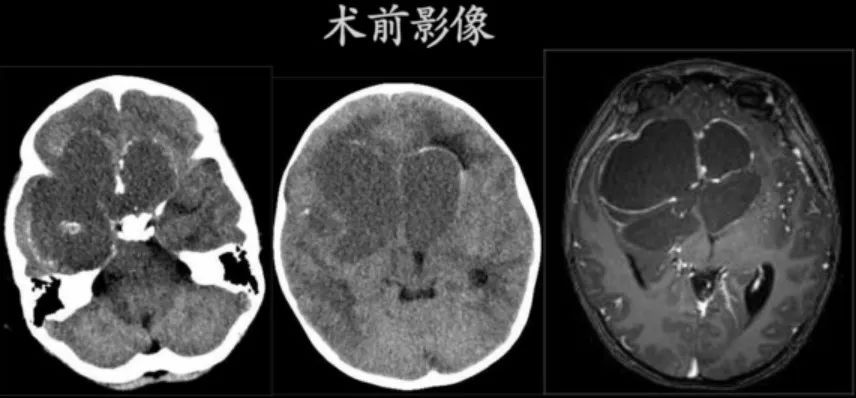

肿瘤巨大、位置特殊,手术刻不容缓!张晨冉立即将小君收入院。一系列术前检查,紧锣密鼓地进行着:头颅CT、磁共振等影像学检查,视力、视野、眼底的相关检查,及详细的体格检查。检查发现,小君右侧瞳孔扩大,对光反射消失,无光感,右眼视力完全丧失,左眼视力仍基本正常。

术后,在小儿重症监护室和儿神经外科医护团队的精心照料下,小君顺利度过了过山车似的电解质紊乱、垂体激素紊乱等难关,张晨冉亦是坚持每天两次查房,积极关注小君伤口、尿量、电解质及垂体功能情况。复查CT及磁共振可见肿瘤全切,没有明显神经系统受损的阳性体征。